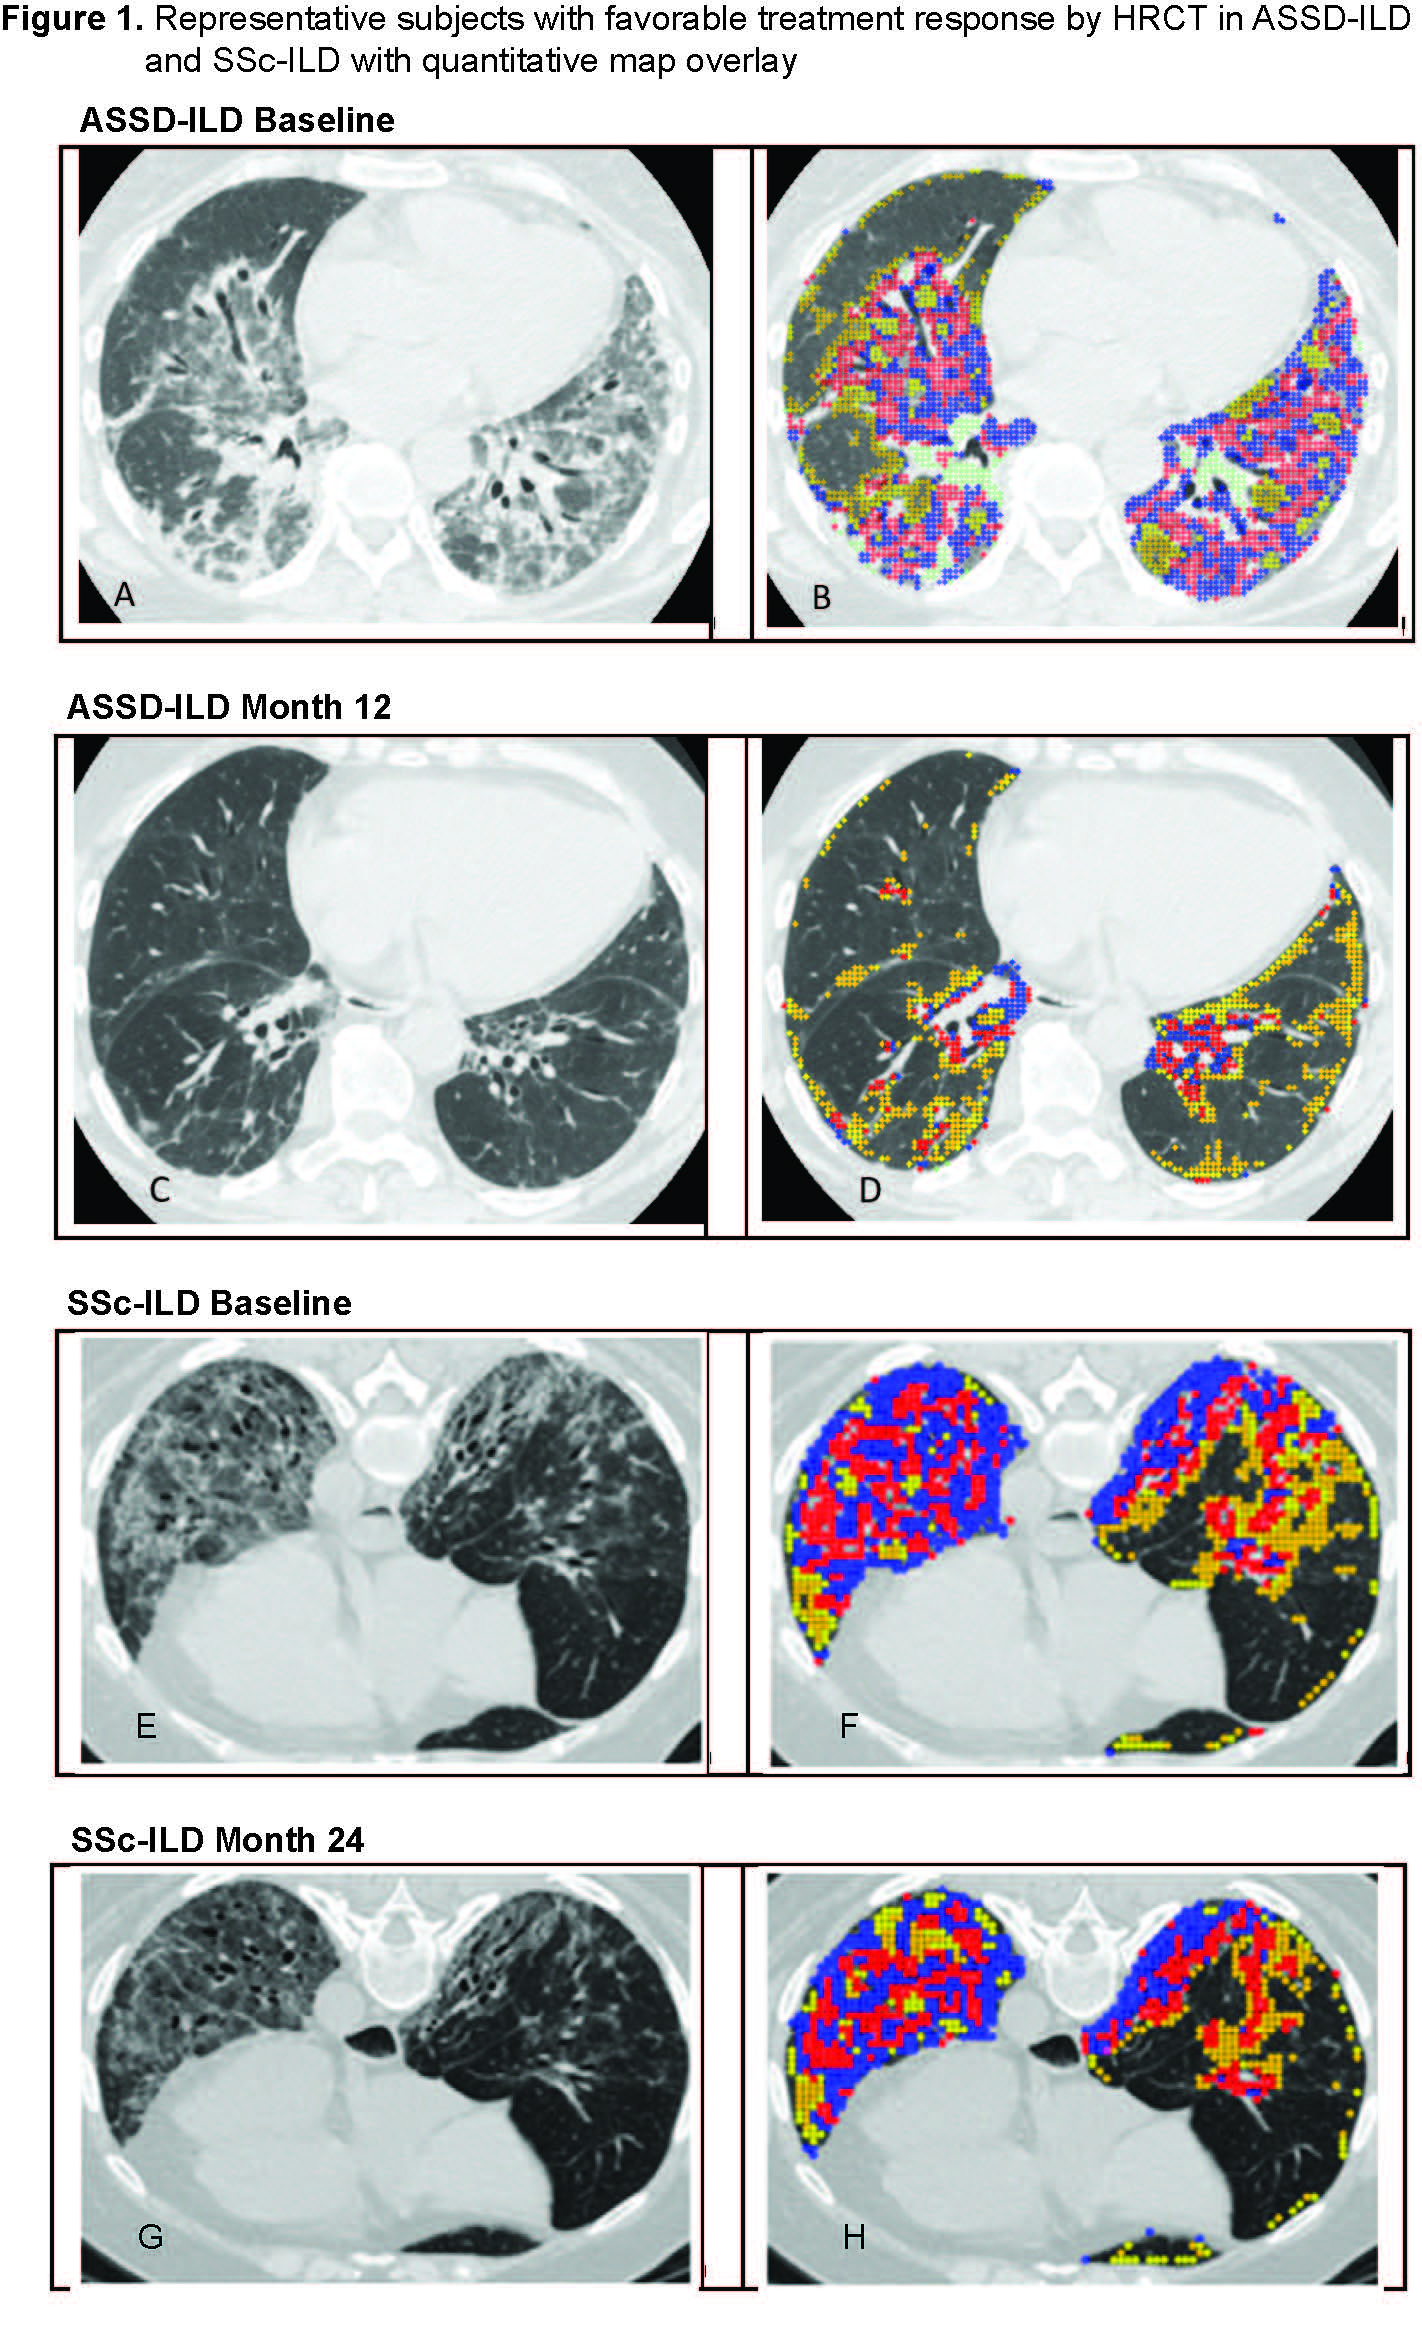

Results: Baseline characteristics are described in Table 1. The ASSD-ILD group had lowest forced vital capacity(FVC) and diffusing capacity (DLCO) and highest quantitative scores for ground glass (QGG), fibrosis (QLF) , honeycombing (QHC) and total sum of disease (QILD) among the 3 cohorts. Zone of maximum involvement was shared throughout upper, middle and lower zones in ASSD- and Myositis-ILD, unlike SSc-ILD where 94% had maximum disease in the lower zones of the lung. Visual review of the ASSD-ILD and Myositis-ILD images revealed a pattern distinct from SSc-ILD (Figure 1). In ASSD- and Myositis-ILD, there are areas of confluent fibrosis that mimic organizing pneumonia with fibrosis and volume loss. Also, the disease extends to the periphery of the lung, unlike SSc-ILD which tends to spare the periphery. Both diseases demonstrate ground glass opacity and reticulations with bronchiectasis. In comparing subjects that showed favorable treatment response from the two clinical trials, the ASSD-ILD patient showed marked improvement in CT images (Figure 1-A to C) which was also reflected in changes in their quantitative scores (Figure 1-B to D), whereas in the SSc-ILD subject the improvement was more subtle (Figure 1 E,F to G,H). Mean changes in lung physiology and quantitative CT scores over the trial period demonstrated that QLF scores in the ASSD-ILD cohort showed greater improvement compared to the SSc-ILD cohort despite its shorter follow up time and the lack of differences in changes in FVC or DLCO between the groups (Table 2).

Representative subjects with favorable treatment response by high-resolution computed tomography (HRCT) in ASSD-ILD (A-D) and SSc-ILD (E-H). In the quantitative map overlay (right panel), the sum of the blue and red areas represents the extent of quantitative lung fibrosis (QLF), and the yellow area represents the extent of quantitative ground glass(QGG). The sum of all the colors represents quantitation of total ILD (QILD).

(A,B) In ASSD-ILD, there is mixed ground glass and consolidative infiltrates in lower lobes with thick walled reticulations and mild bronchiectasis with some volume loss. The pattern of fibrosis is inconsistent with UIP and favors but not classic for organizing pneumonia. Follow up image (C,D) demonstrates significant decrease in the lung infiltrates with residual reticular lines and limited loss of volume. The quantitative overlay shows significant decrease in QLF and QGG. (E,F) In SSc-ILD, HRCT at baseline demonstrates lower lobe course ground glass opacity with reticulations and traction bronchiectasis/bronchiolectasis and relative subpleural sparing best seen on the left side. (G) After 24 months, there is subtle decrease in density of ground glass and extent and thickness of reticulations but persistent bronchiectasis/bronchiolectasis. (H) Quantitative map overlay at 24 months demonstrates decrease in QLF shaded as red and blue.